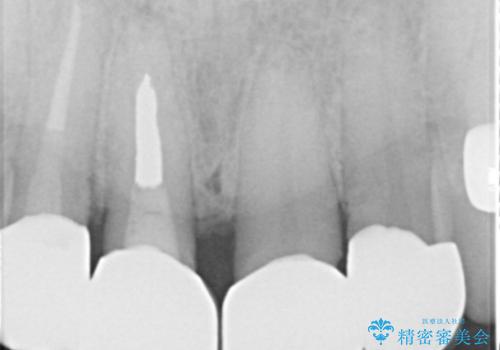

神経を取っている右上2番目の歯は根尖部に病巣があったため根管治療をした上で土台を立て、被せ物の作製を行いました。右上1番目の歯は他院にてとても大きく深い金属の土台が入れられており被せ物の色調に影響を与えていましたが、すべて取りきることのリスクが高いため途中まで除去し目立ちにくいファイバーコアで補強と色調の改善を行いました。